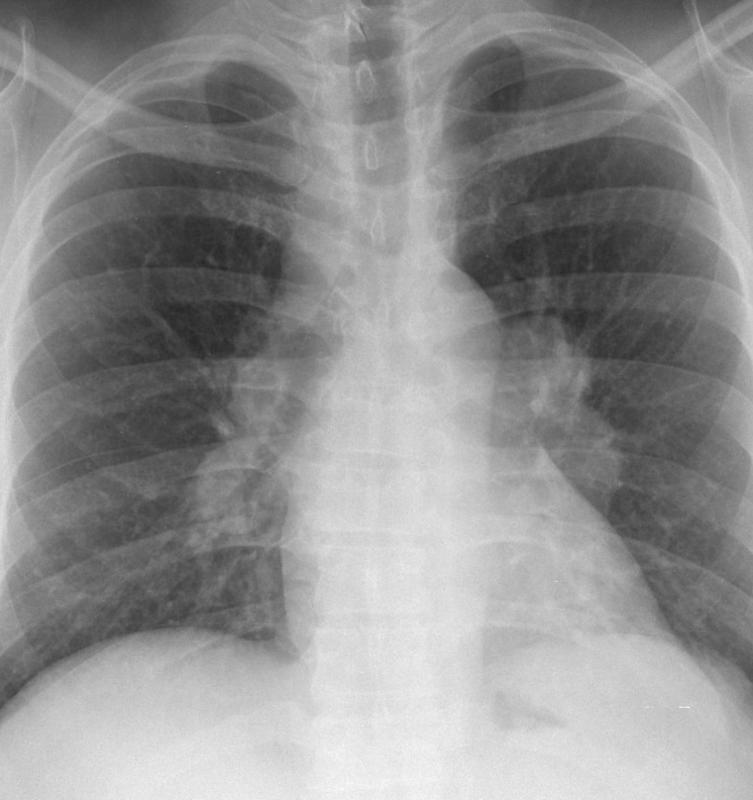

Gallery Mediastinum Lymphoma 2a

2a